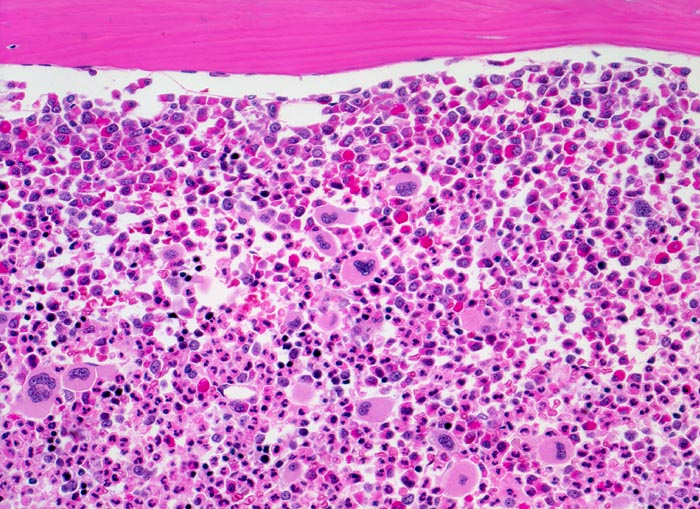

PathoPic – image database / PathoPic ID 3898 - chronische myeloische Leukämie (CML)

chronische myeloische Leukämie (CML)

Knochenmark, Beckenkamm

Extrem hyperzelluläres Knochenmark ohne Fettzellen.

Hochgradig gesteigerte voll ausreifende neutrophile Granulopoese. Erkennbar sind verschiedene Reifungsstufen der Granulopoese, wobei die unreiferen Vorstufen (Myelozyten, Promyelozyten) bevorzugt entlang des Spongiosabälkchens paratrabekulär lokalisiert sind. Zur Mitte des Markraumes hin folgt die Reifungszone mit Prädominanz segmentkerniger Neutrophiler. Die normoblastäre Erythropoese ist fast vollständig verdrängt. Typisch ist die Vermehrung kleiner Megakaryozyten mit hypolobulierten Kernen.

Müdigkeit und Gewichtsverlust. Ausgeprägte Leukozytose, Basophilie und leichte Anämie. Palpable Milz.

Histologie

200